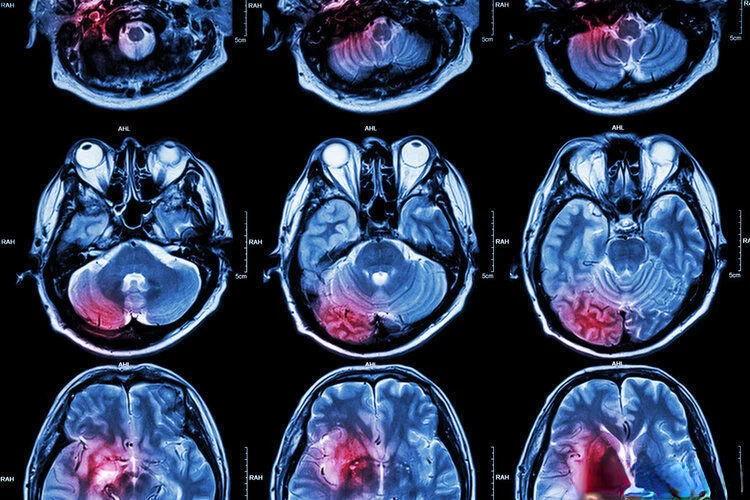

2021年,发表在国际医学杂志《卒中(Stroke)》上的研究指出,每天适当摄入适量的花生,可以预防以缺血性卒中为主的脑血管疾病!

无论男女,每天摄入4~5颗花生的参与者与不吃花生的参与者相比,发生小中风、缺血性卒中、出血性脑血管病的风险分别降低了16%、20%、13%。